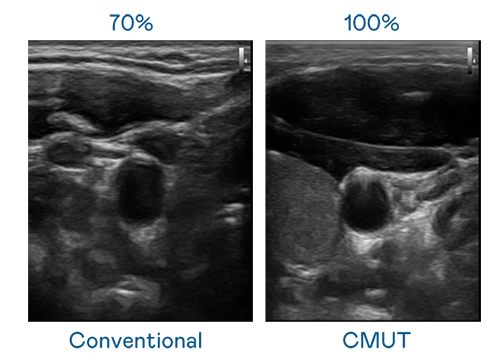

CMUT 技术是一种用电容式微机电元件来产生超音波讯号的技术。与传统 PZT 压电式技术相比,CMUT 频宽增加 30%,更宽频的超音波讯号让影像解析度大幅提升,是实现高影像品质医疗超音波扫描、促进精准医疗发展的关键技术。

超音波影像的解析度高低,首先取决于探头能发出的讯号频宽。AG官网 CMUT 可提供高清晰的超音波讯号,提供高频宽、高灵敏度、影像纹理细节更高的超音波影像,协助医护人员缩短影像判读时间及利用精准的医疗影像进行诊断。